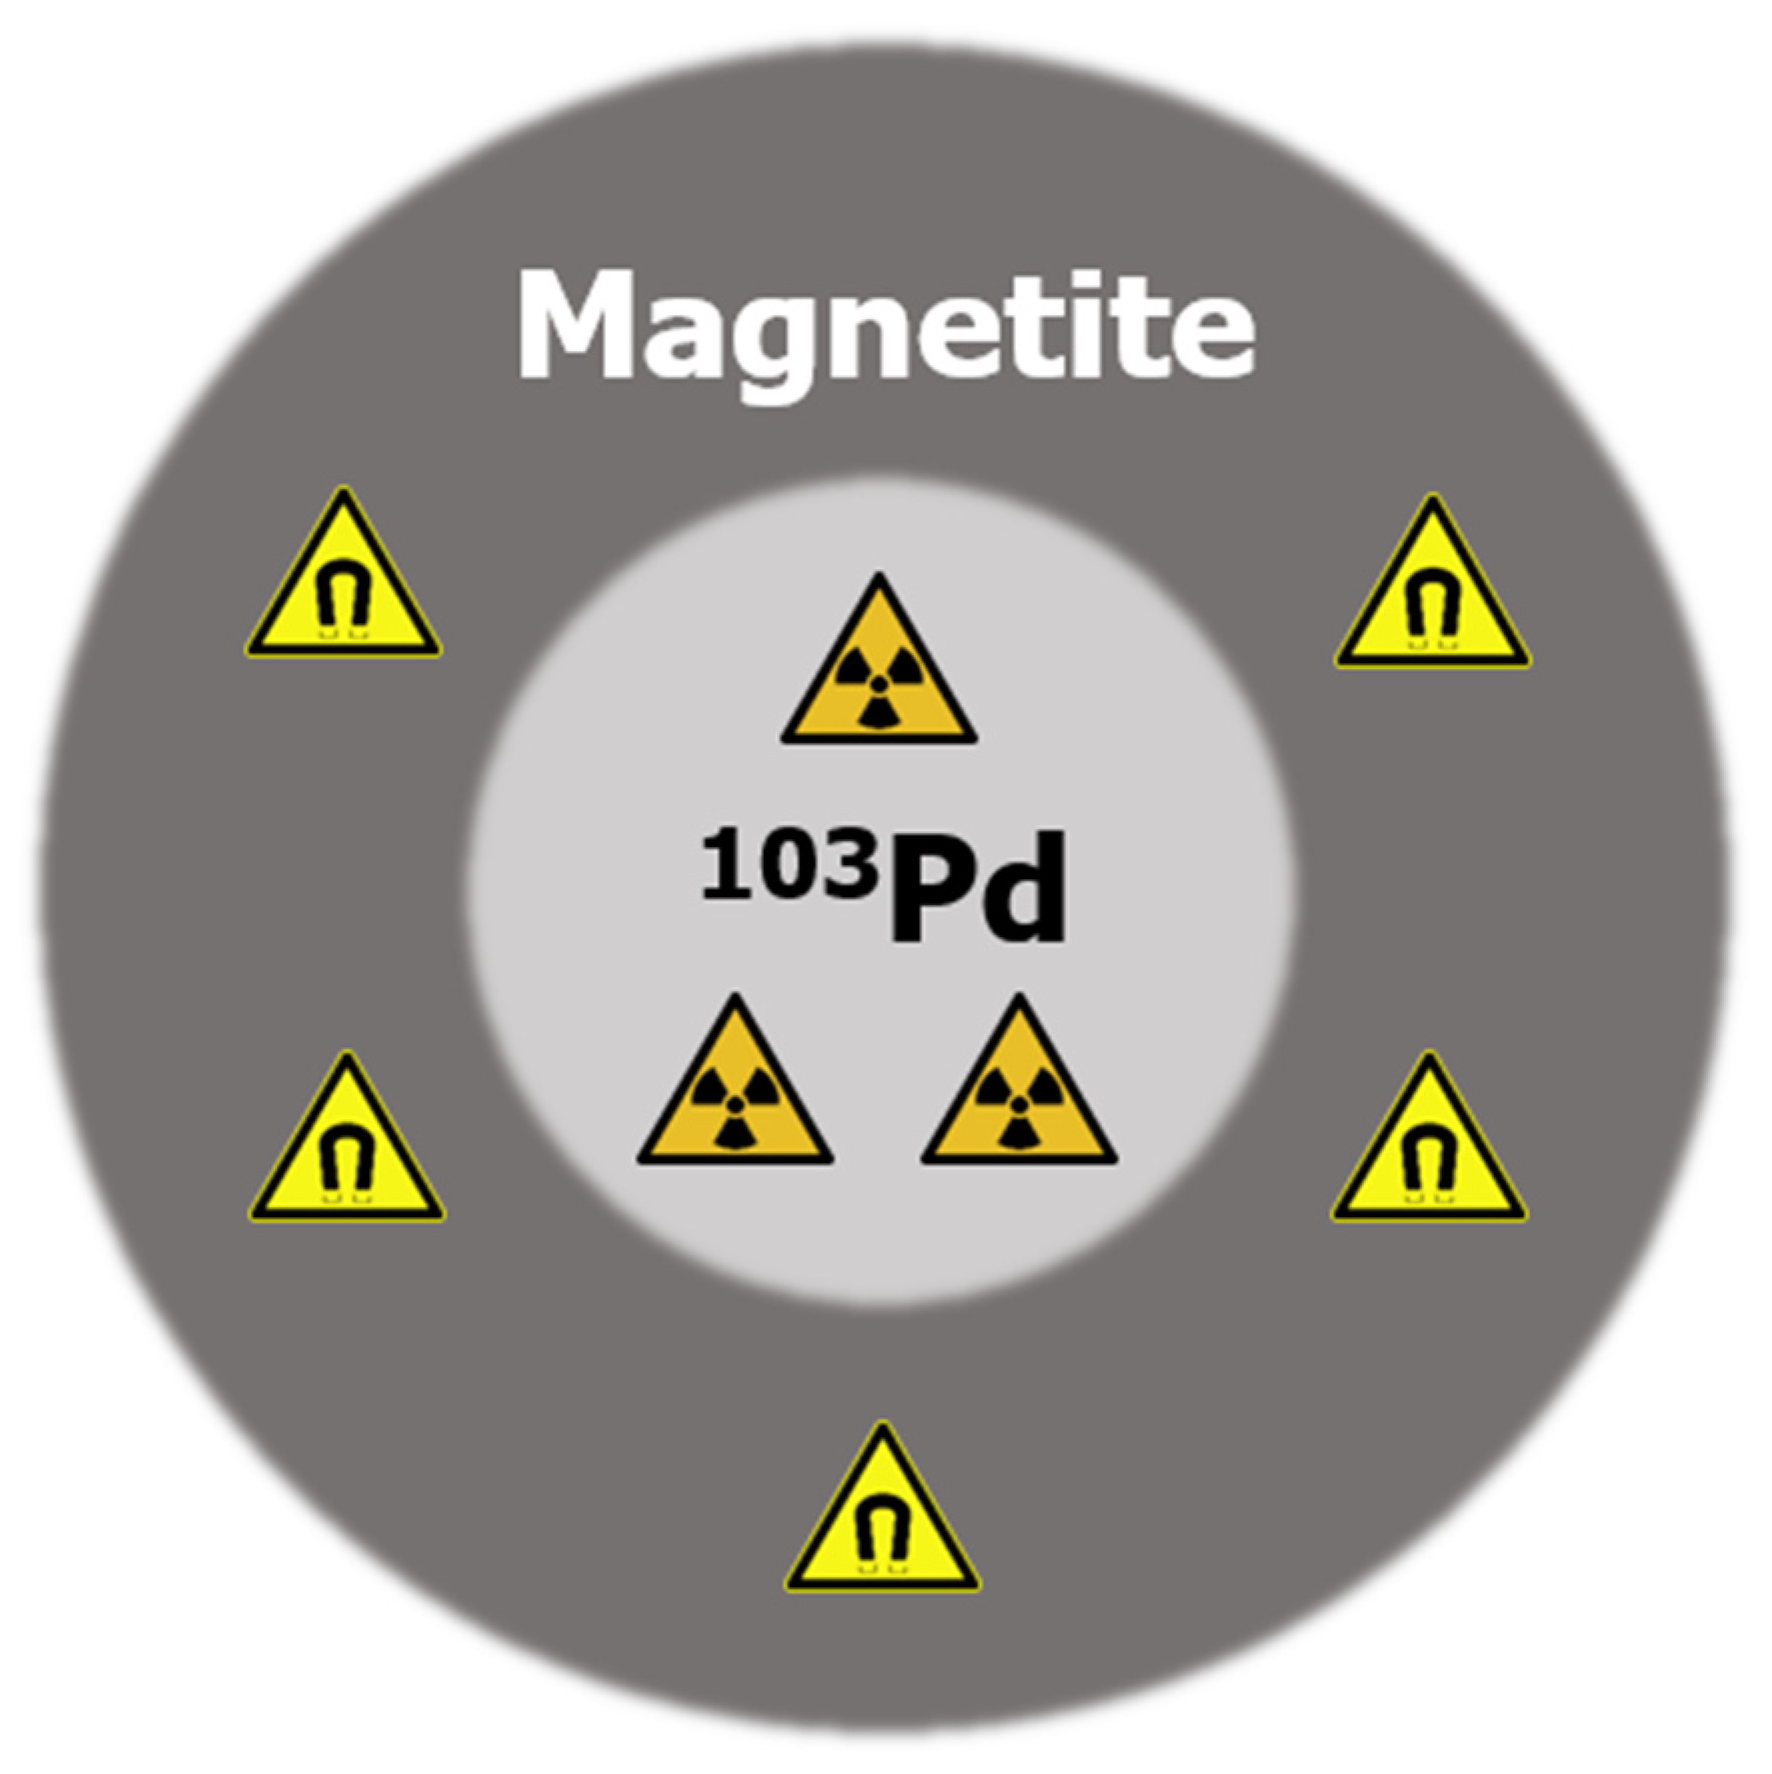

2.2. Single Nanoparticle Simulations